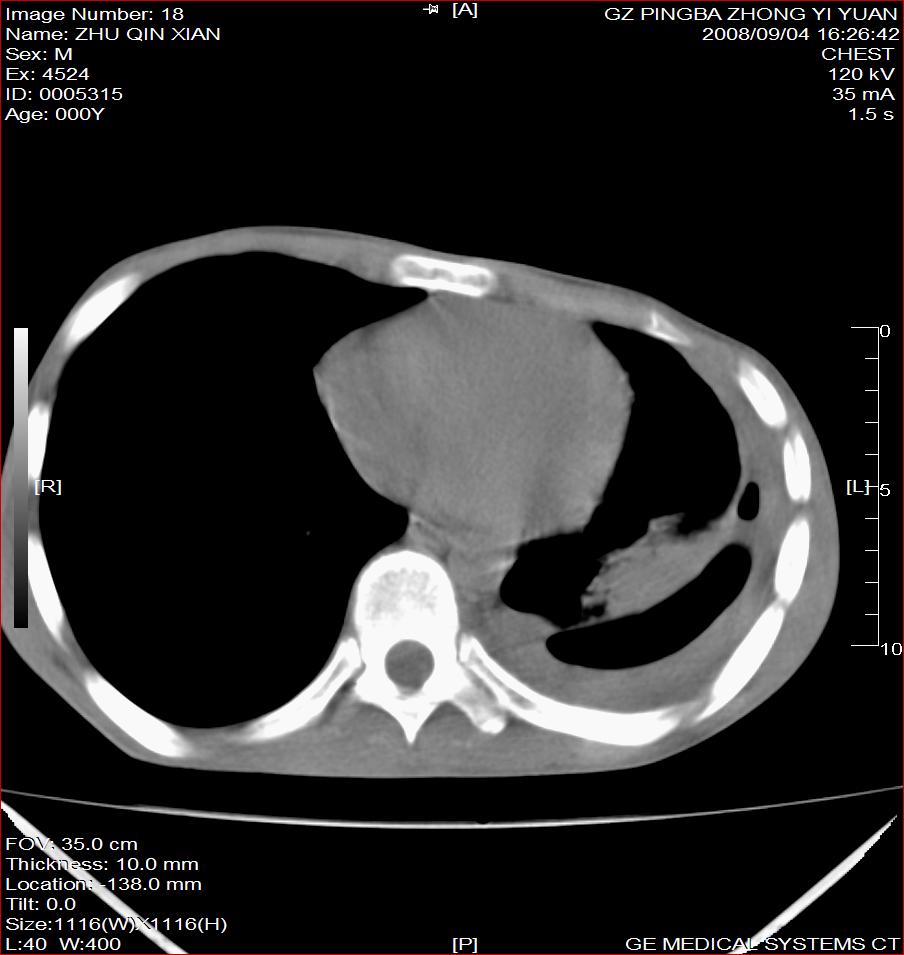

以下是引用随光逐影在2008-9-4 20:05:00的发言:[br]1)考虑两肺结核。2)左侧胸膜炎(胸膜肥厚、粘连,胸腔积液)。3)左侧局限性气胸。

以下是引用子十在2008-9-4 19:34:00的发言:[br]左上肺结核并空洞及双肺播散。节段性肺不张、胸腔积液、胸膜肥厚粘连。[br]